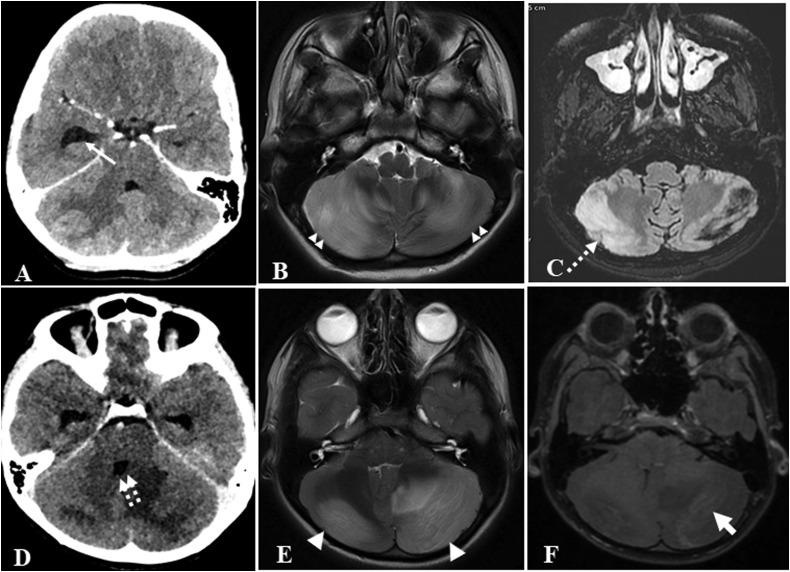

Acute Fulminant Cerebellitis in Children with COVID-19 Infection: A Rare But Treatable Complication.

https://cdn.ncbi.nlm.nih.gov/pmc/blobs/f554/7997024/76ae30806e7d/gr1_lrg.jpg